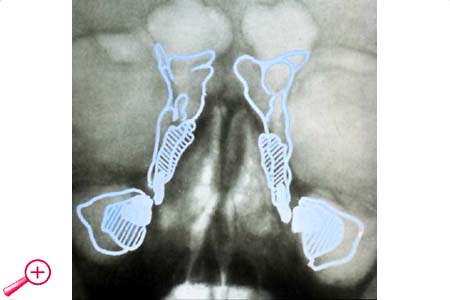

6. Missbildungen der Nasennebenhöhlen

Aplasien und Hypoplasien der Nasennebenhöhlen sind klinisch kaum von Bedeutung.